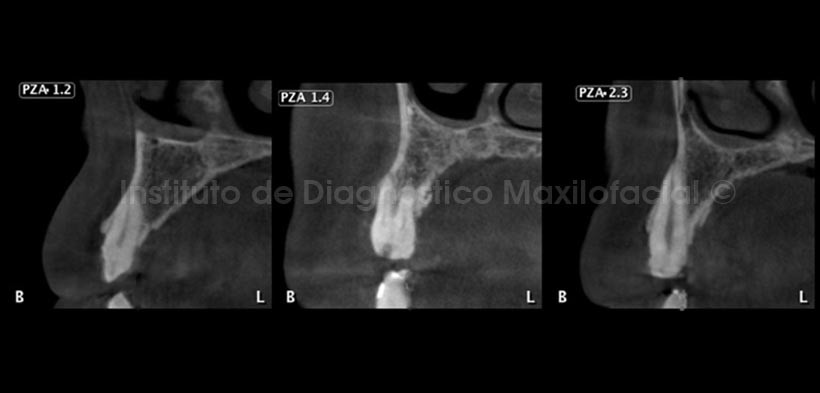

En cortes transaxiales (Fig.3 y 4) se observan diferentes piezas dentarias, notando el delgado grosor del esmalte en todas ellas, además se observan cavidades, las cuales pueden estar asociadas a este tipo de anomalía.